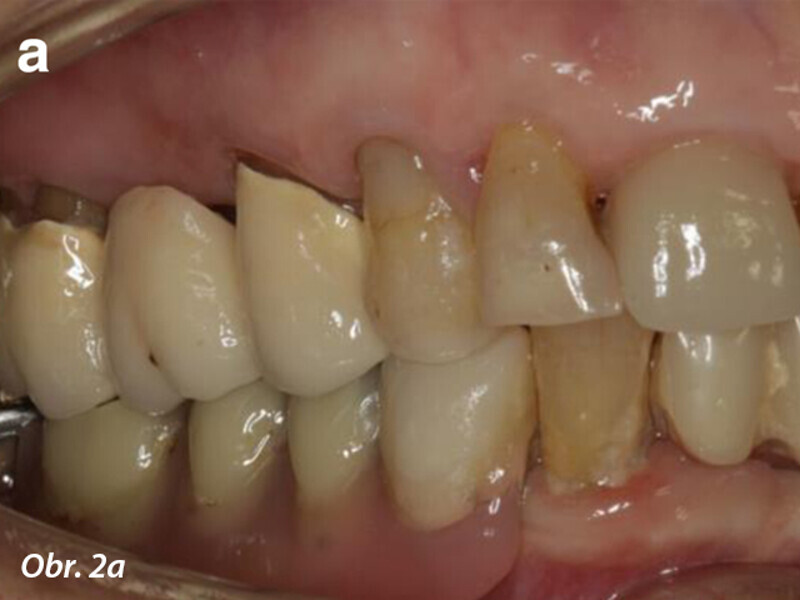

Počítačem asistované, šablonou se řídící okamžité zavedení a zatížení implantátu v dolní čelisti